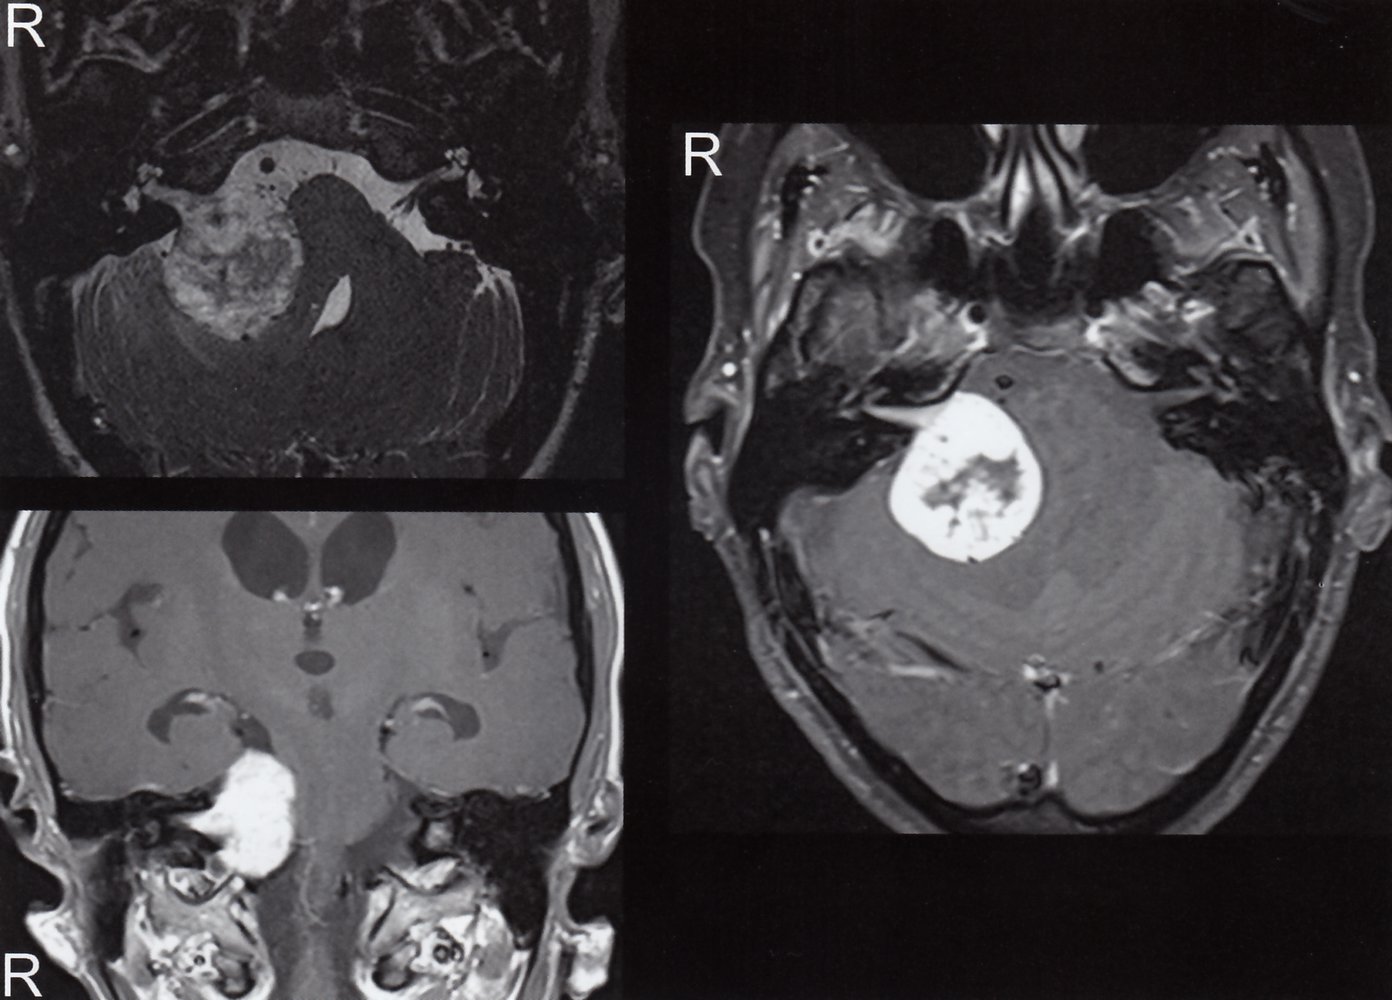

• Contrast MRI (imaging modality of choice)

• Recommended in patients with abnormal audiometric testing or high clinical suspicion of acoustic neuroma (cerebellopontine angle syndrome)

• CT with and without contrast is an alternative for those who cannot undergo MRI.

• Shows an enhancing lesion by the internal auditory canal, with possible extension into the cerebellopontine angle